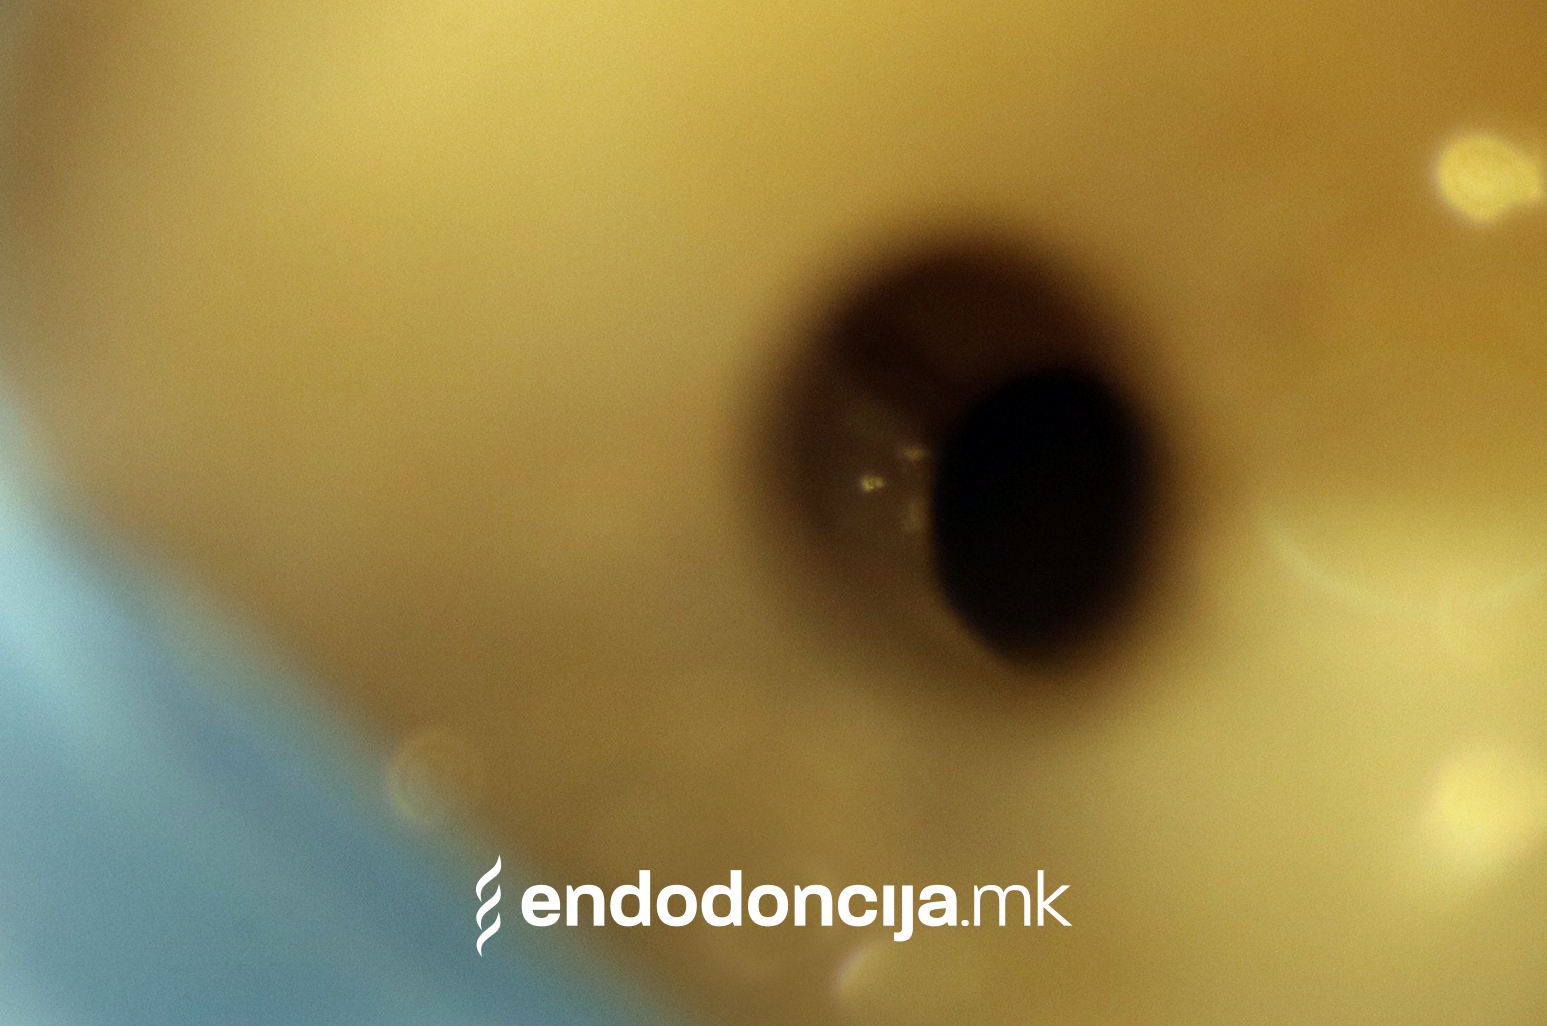

Она што е импресивно е прецизноста на микроскопските третмани. Дури и кога каналите се потешко достапни, може да се лоцираат и исчистат така што релапсите се со помала веројатност. Спротивно на тоа, скриените канали често остануваат неоткриени во конвенционалниот третман на коренскиот канал и затоа не можат да се чистат. Бактериите можат да се размножуваат таму без пречки и да предизвикаат воспаленија. Ова често останува незабележано со години додека не се појави забоболка, а со тоа и компликации.

Употребата на микроскоп исто така овозможува детектирање пукнатини или фрактури што може да предизвикаат болка или воспаление.